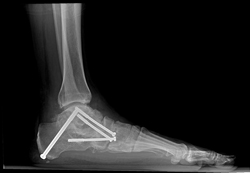

(Arriba) Radiografía de un pie normal. Observe que la línea que pasa por el centro del hueso del tobillo (astrágalo) y la línea que pasa por el resto del pie son paralelas, lo que indica un arco normal. (Abajo) En esta radiografía, la líneas se bifurcan, lo que indica una deformidad por pie plano.